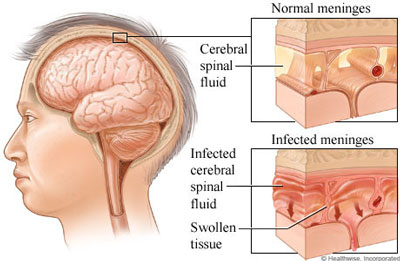

قیمت: 32٬000 تومان - دسته بندی فایل: پاورپوینتپاورپوینت مننژیت Meningiti

فروش ویژه پاورپوینت حرفه ای مننژیت Meningiti با تخفیف استثنایی فقط 49590 هزار تومان تعداد اسلاید : 10 اسلاید